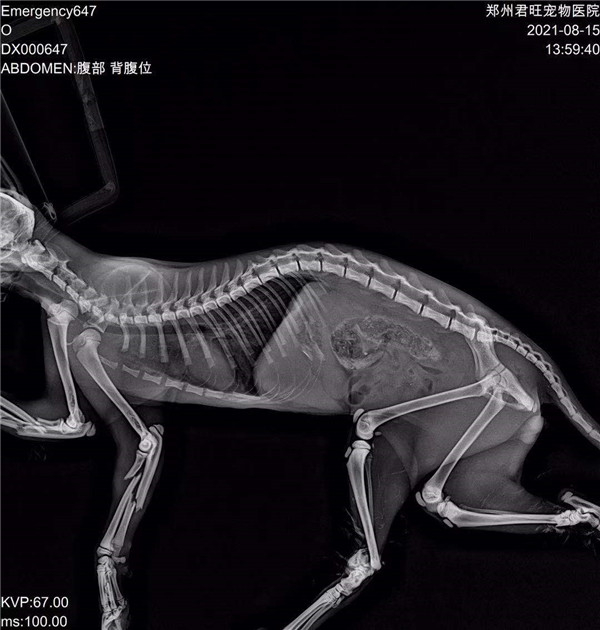

郑州市君旺宠物医院的翟医生,望着眼前面目全非的九福,微微锁起了眉头,简单检查过之后,就得出了判断:九福是被人虐待了。因为它的四条腿均是对称性骨折,两只前腿更是粉碎性骨折,满口牙也被拔掉了。“这绝对不是车祸,或者动物撕咬造成的,只能是人。”